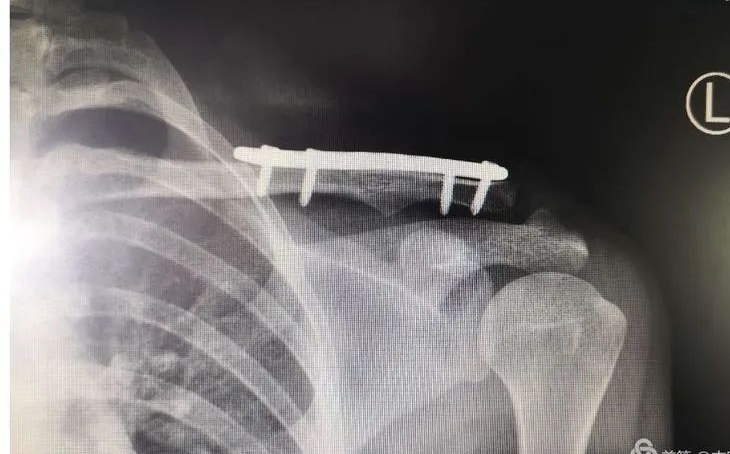

# علاج كسور الطرف القريب لعظمة الترقوة: نظرة شاملة وحديثة تعتبر كسور الطرف القريب لعظمة الترقوة، أي الجزء الأقرب إلى ع…

# علاج كسور عظمة الترقوة بتقنية التدخل الجراحي المحدود (MIPO): دليل شامل تُعد كسور عظمة الترقوة من الإصابات الشائعة في …

# تقنية التثبيت الكامل بالخيوط الجراحية لعلاج الكسور غير المستقرة في الطرف البعيد لعظمة الترقوة تُمثل كسور الطرف البعيد…